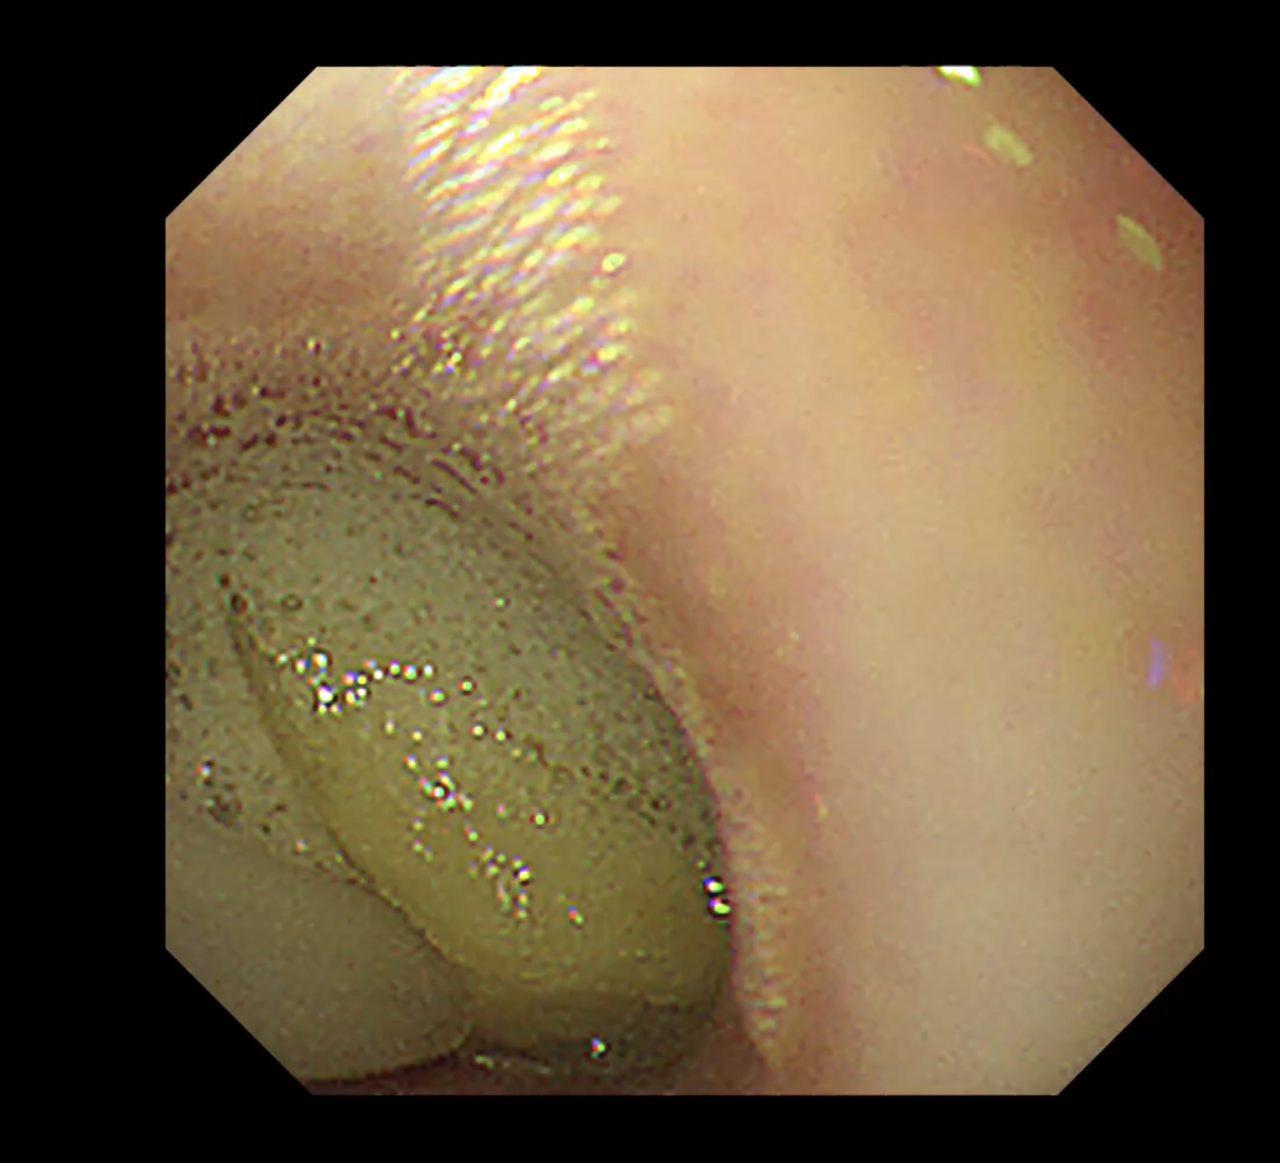

- 処置:内視鏡ガイドでストマックチューブを用いて慎重に胃内に落とし込む。

- 経過:摘出後は嘔吐や食欲不振もなく、順調に回復。軽度の炎症あり。